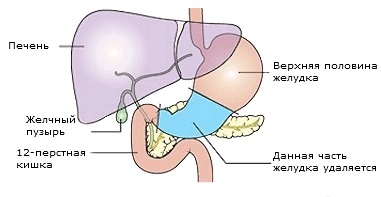

În cazul în care cancerul este localizat în compartimentul inferior al stomacului, care intră în duoden 12, este posibila indepartarea chirurgicala a unei portiuni a stomacului. Această operație se numește gastrectomie. Volumul de funcționare depinde de localizarea tumorii în interiorul corpului. După o intervenție chirurgicală, capacitatea stomacului ar fi semnificativ mai mică, dar supapa (sfincterul cardiac) între stomac și esofag va rămâne în vigoare. cicatrice postoperatorie va avea loc peste abdomen.

Diagrama care arată îndepărtarea unei părți din stomac în etapa Billroth I